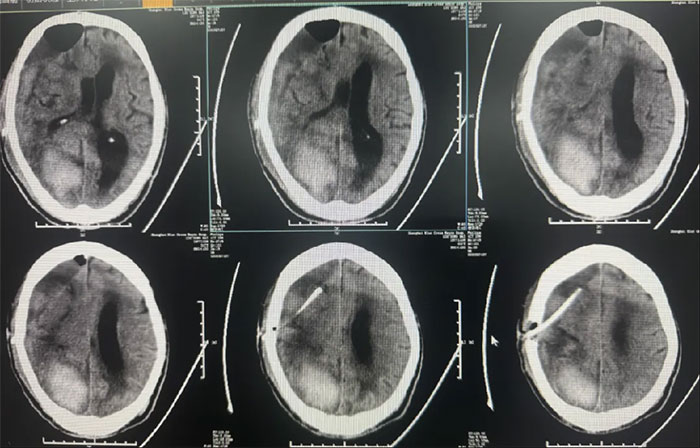

右頂枕葉出血,右側額顳頂部亞急性硬膜下血腫,大腦鐮下疝形成。

硬腦膜下鉆孔引流術(長程引流管),引流管自右側鎖骨下皮膚穿出引流;

2025-02-18(發(fā)病后17天);

患者病情復雜,選擇在局麻下進行,術程順利。